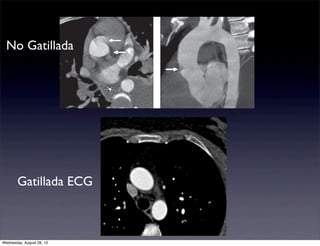

No Gatillada

Gatillada ECG